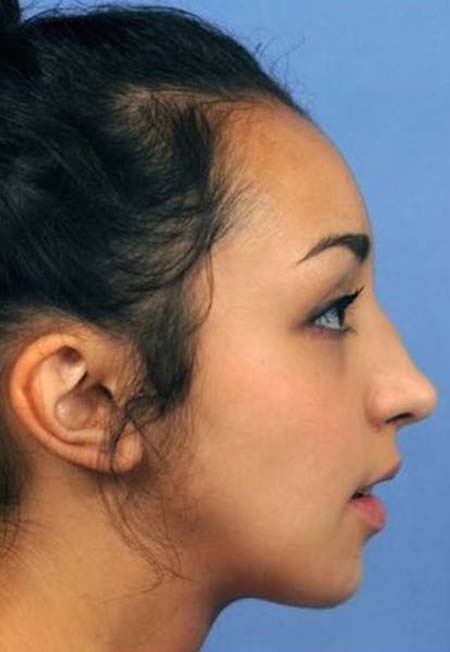

Η Ellie Jones πήρε εκδίκηση. Η συγκεκριμένη κοπέλα, η οποία βρίσκεται στην ηλικία των 20 ετών, δεν βρήκε τα πάντα έτοιμα στη ζωή της. Η Ellie Jones γεννήθηκε με συγγενική παραμόρφωση στο πρόσωπό της. Τα δόντια της δεν ήταν ευθυγραμμισμένα. Ωστόσο, αυτό δεν ήταν το μοναδικό της πρόβλημα. Το σαγόνι της Ellie Jones δεν είχε μεγαλώσει από την ηλικία των 8 ετών.

Το αποτέλεσμα ήταν να δέχεται για το μεγαλύτερο χρονικό διάστημα της ζωής της πειράγματα. Πειράγματα και κοροϊδίες, οι οποίες ερχόντουσαν από άτομα της καθημερινότητας. Μάλιστα, οι συμμαθητές της την επηρέαζαν, καθώς τη χλεύαζαν για την εξωτερική εμφάνισή της. Αυτό είχε ως αποτέλεσμα, η ίδια, να έχει αυτοπεποίθηση σε ιδιαίτερα χαμηλά επίπεδα.

Η ίδια και ο οικογενειακός της περίγυρος αποφάσισαν να μη μείνουν με σταυρωμένα χέρια. Θέλησαν να προχωρήσουν σε μία χειρουργική επέμβαση. Μέσω αυτής της επέμβασης επιδιώκονταν να διορθωθούν όσα ενοχλούσαν την Ellie Jones, τα οποία κρατούσαν και την ψυχολογία της στο ναδίρ.

Η οικογένεια επισκέφθηκε έναν γναθοχειρουργό, ο οποίος βοήθησε στη μεταμόρφωση της Ellie Jones. Το πρώτη χειρουργείο προκάλεσε πολύ πόνο στην 20χρονη. Ήταν ιδιαίτερα δύσκολο σαν χειρουργείο και στο τέλος του έπρεπε να κάνει σωστή διατροφή. Αυτή εμπεριείχε μόνο υγρά για χρονικό διάστημα ενός μηνός, ενώ στο ξεκίνημα δεν μπορούσε να μιλήσει.

Στο χειρουργείο, που ακολούθησε, το οποίο ήταν δεύτερο κατά σειρά μπόρεσε να διορθώσει το πηγούνι της. Έτσι, μπόρεσε να μεταμορφωθεί και να φτιάξει παράλληλα και την ψυχολογία της.

«Η χειρουργική επέμβαση δεν έχει αλλάξει μόνο τον τρόπο που κοιτάζουν την Ellie, αλλά και τον τρόπο που η ίδια βλέπει τον εαυτό της. Η αυτοπεποίθηση της έχει αυξηθεί και η ίδια έχει εξελιχθεί σε μια όμορφη νεαρή κοπέλα».